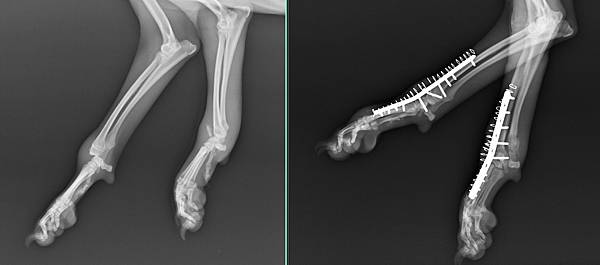

有天從三樓掉下來

雙手腕骨折脫臼

手術前